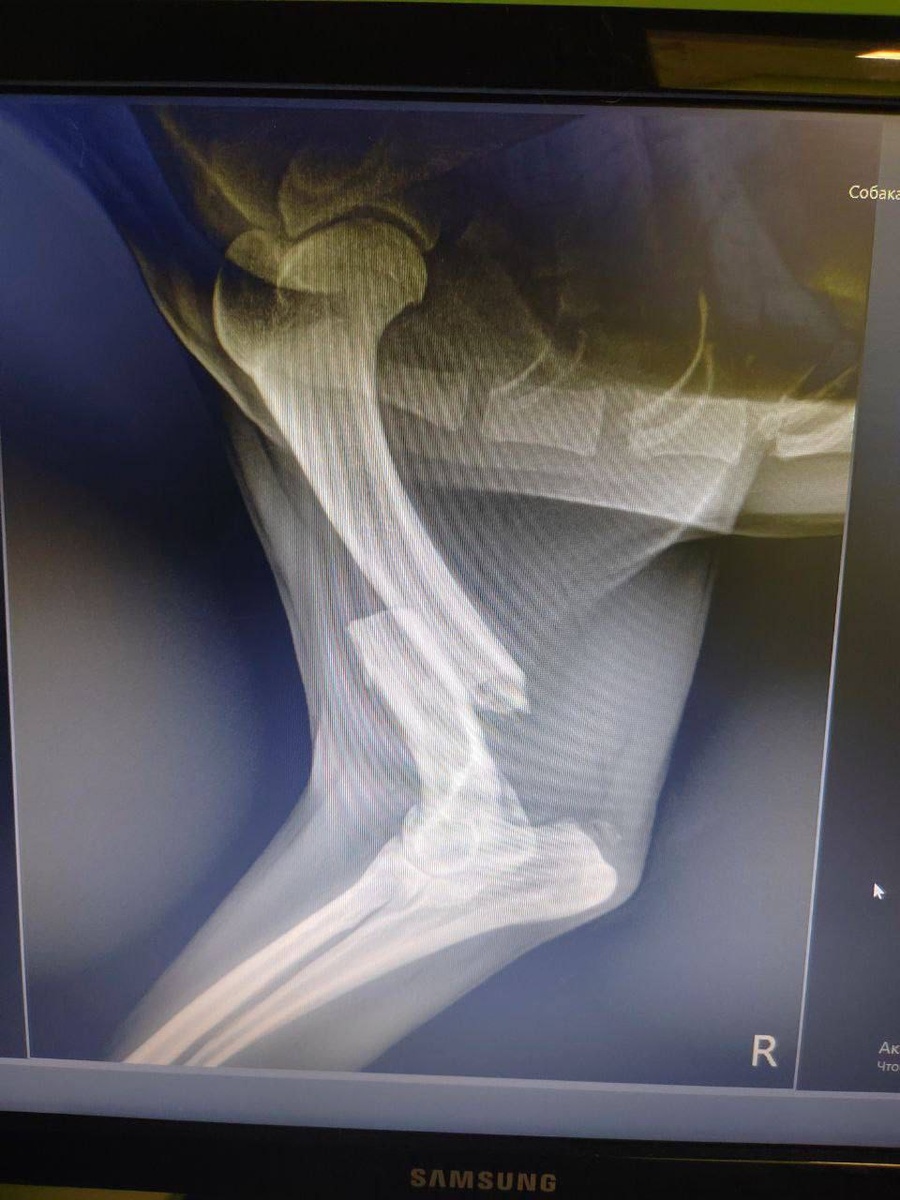

Бездомный добродушный песик совсем не опирался на одну из лапок и выглядел очень грустным. Ко мне обратилась молодая девушка, которая впервые нашла собаку с травмой. Она обзвонила все приюты и все отказали. Конечно, ведь требования к приютам настолько строгие, что вот таким действительно бездомным путь туда закрыт.

Разве можно позволить такому лапочке проходить всю оставшуюся жизнь на трех лапках? Вот и подумала, что у нас с вами получится оплатить операцию этой милой собачке.

Договорилась я с Натальей Андреевной об операции и стационаре, а она оказалась как раз была недалеко от того места, где сидел кобелёк, поэтому ветеринары сами заехали и забрали его в клинику. Вот это уровень ветеринарной помощи, друзья!